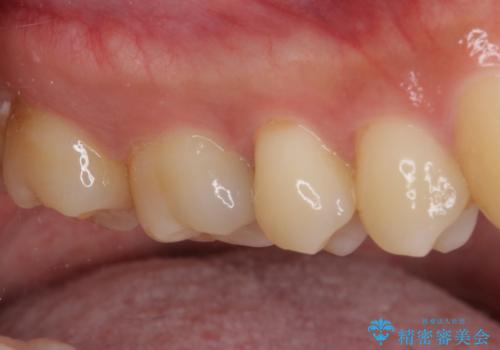

フロスが引っかかる セラミックインレーによるむし歯治療

- ウェブサイトの症例(https://seimitsushinbi.jp/case/9473/)を見て、同じようにフロスが引っかかるとのことで来院された患者様です。

虫歯を除去した後、セラミックインレーにて修復治療を行うこととしました。

セラミックインレー装着後はフロスの引っかかるストレスから解放され、患者様には大変満足していただきました。